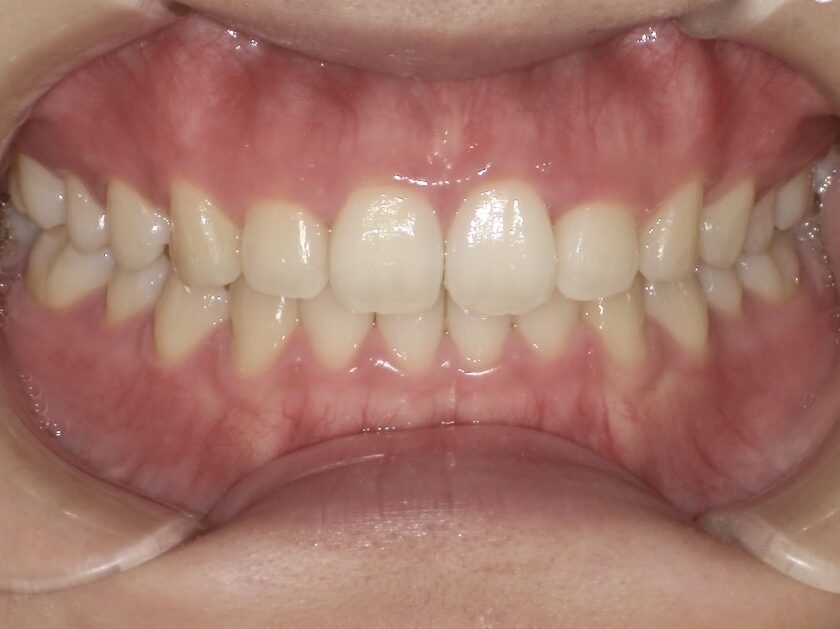

前歯のすき間が気になるを主訴に当院を受診され、前歯部空隙歯列(歯と歯の間に隙間が空いている状態)・過蓋咬合(上の歯が下の歯を深く覆いかぶさっている状態)・下顎前歯叢生(ガタガタ)を認めました。

IPRを使用してマウスピース型矯正装置(インビザライン)を使用し過蓋咬合及び叢生の改善を行いました。